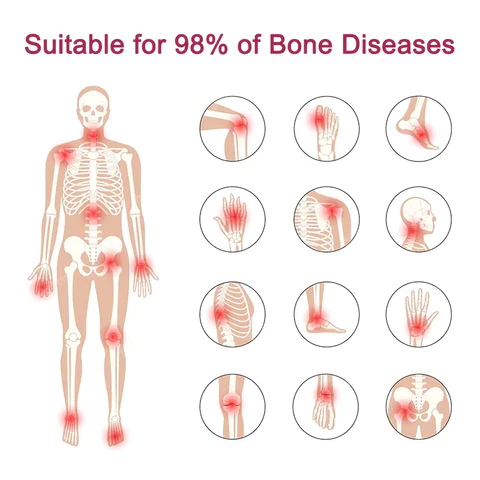

PERFECTX CAN PROVIDE RAPID PAIN RELIEF AND SAFELY AND EFFECTIVELY ELIMINATE 99% OF ORTHOPEDIC PROBLEMS SUCH AS OSTEOARTHRITIS, RHEUMATOID ARTHRITIS, BURSITIS, TENDONITIS, OSTEOPOROSIS, GOUT, CARPAL TUNNEL SYNDROME, LIGAMENT SPRAINS AND STRAINS, BUNIONS, AND TENNIS ELBOW WITHIN 2 WEEKS.

Orthopedic diseases can occur due to a variety of factors, including age-related degeneration, overuse or injury, genetics, and certain medical conditions such as diabetes or rheumatoid arthritis. Poor posture, poor nutrition, and certain types of work or sports can also increase the risk of developing an orthopedic condition. According to statistics, 35% of the population in the US and Europe suffer from joint problems, with varying degrees of joint problems in every five people. The milder cases include arthritis, rheumatism, and gout, with symptoms such as pain, stiffness, swelling, difficulty in movement, fatigue, and loss of range of motion. Severe cases can result in joint deformities, fever, and intense joint pain, which can lead to long-term pain and disability. In extreme cases, orthopedic diseases can even lead to life-threatening complications.